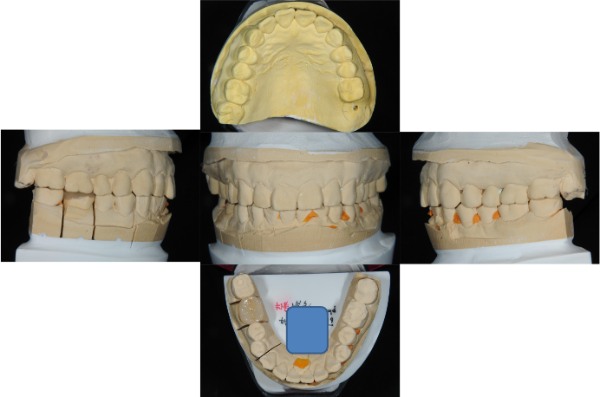

上面弓,咬合器